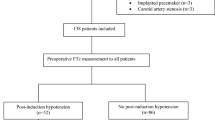

A total of 102 participants were recruited for this trial. Seven were excluded: 3 received intravenous propofol due to postintubation hypertension, 3 had inadequate ultrasound images, and 1 declined study participation (Fig. 2). Among the remaining 95 enrolled participants, there were 61 patients with hypotension and 34 with non-hypotension. Patients who developed hypotension had a higher ΔFTc in the carotid artery. The decrease in ΔFTc was greater in hypotension (−21.42 ± 6.06 mmHg) than in non-hypotension (−15.68 ± 3.59 mmHg) (p < 0.001) (Fig. 3).